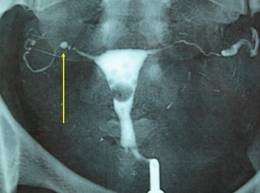

L’Hystérosalpingographie permet de juger de la perméabilité tubaire à la recherche d’une sténose, d’une obstruction ou de diverticules évoquant ou encore, une mauvaise diffusion du produit de contraste traduisant l’existence d’adhérences pelviennes. Elle peut aussi montrer des anomalies endocavitaires: synéchie, myome sous muqueux ou polype, adénomyose.